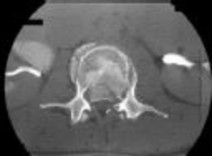

A 73-year-old man with diabetes comes to the emergency department with

low back pain and fever. His blood cultures are positive for methicillin-resistant Staphylococcus aureus (MRSA). He has no neurologic signs or symptoms of lumbar radiculopathy or cauda equina syndrome. Figure 1 shows his axial T2-weighted MRI, and an arrow marks the junction of the theca sac and the epidural abscess. What is the most appropriate recommendation for this patient?

4. Anterior diskectomy, followed by antibiotics Discussion: C

Epidural abscess once was considered an absolute indication for surgery. Nonsurgical management has been gaining ground for select patients, however. Kim and associates reported the results of a large series of patients treated for epidural abscess. Many of the patients were treated successfully without surgery, and nonsurgical management was chosen for many of the patients who presented without signs or symptoms of neurologic dysfunction. The authors identified four risk factors that were highly associated with the failure of nonsurgical management, however, including age older than 65 years, diabetes, MRSA, and neurologic compromise.